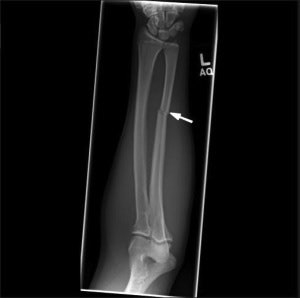

In addition, wrist and forearm fractures are particularly common, such as the classic Colles fracture. "Nightstick" fractures may also occur when a victim pronates and flexes at the elbow to block an overhead blow, exposing the ulna to direct impact, they wrote.

An anteroposterior radiograph of the left forearm of a patient demonstrates an acute minimally displaced fracture of the ulnar diaphysis (white arrow), compatible with a “nightstick fracture.” Image courtesy of Radiologic Clinics of North America."Better characterizing these patterns can help diagnostic radiologists improve their ability to identify cases of potential intentional injury among cases of purportedly accidental trauma and ultimately serve as a first step in improving their sensitivity for physical elder abuse," the authors wrote.